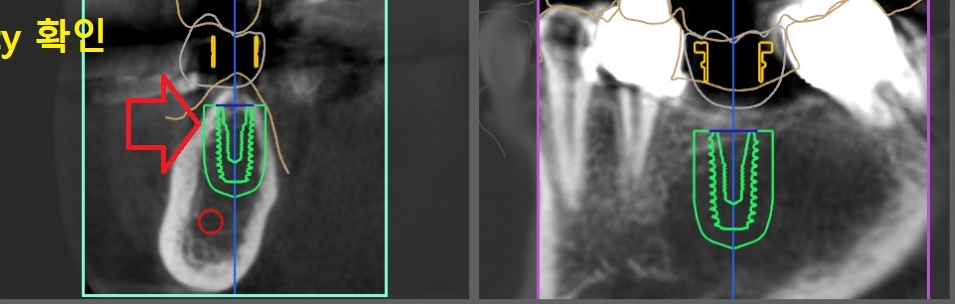

디지털(네비게이션) 임플란트 분석 1

디지털(네비게이션) 임플란트 분석 3

컴퓨터 분석을 토대로 가이드를 만들어

디지털 임플란트 를 심어 드렸습니다.